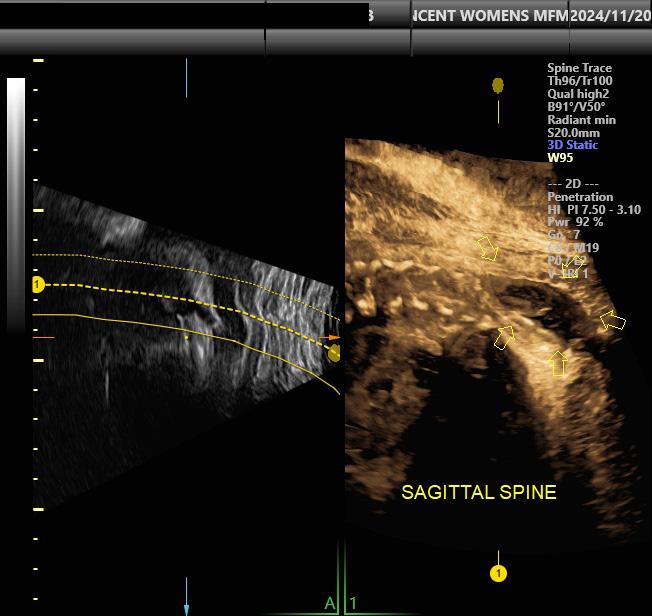

Every pregnancy is unique — and when questions arise, getting answers quickly can bring peace of mind. At Ascension St. Vincent Women and Infants Hospital, our experienced maternal-fetal medicine specialists are ready to see you sooner, combining advanced imaging technology with compassionate support. Because you deserve to feel confident about your care — and your baby’s future.

Find a specialist at ascension.org/IndianaMFM or scan the QR code to learn more.